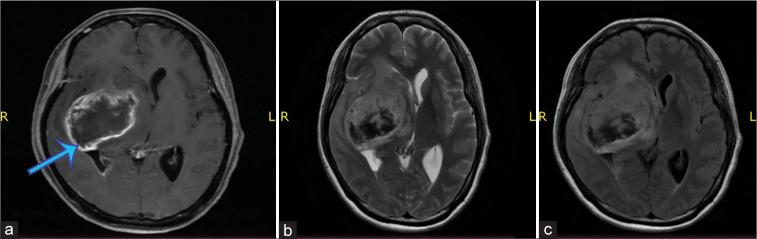

A 64-year-old female presented with headache and dizziness, along with abdominal pain for 2 weeks before being admitted. The abdominal computed tomography (CT) scan showed a kidney tumor. The patient developed left hemiplegia, and the brain CT scan showed an intracranial tumor. The patient suggested for radical nephrectomy and craniotomy tumor removal. Histopathology of the kidney and brain tumor revealed two different features, which showed RCC and GBM. Immunohistochemistry result confirmed the diagnosis of GBM and IDH1 wild type; coexistent with clear cell RCC.

一名64岁女性,入院前2周出现头痛、头晕以及腹痛症状。腹部计算机断层扫描(CT)显示肾脏有肿瘤。患者出现左侧偏瘫,脑部CT扫描显示颅内有肿瘤。建议患者进行根治性肾切除术及开颅肿瘤切除术。肾脏和脑部肿瘤的组织病理学显示出两种不同特征,分别为RCC和GBM。免疫组织化学结果证实为GBM且IDH1野生型;与透明细胞RCC共存。